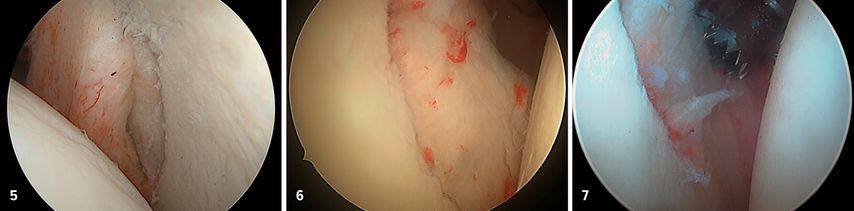

Zur definitiven Fixation stehen unterschiedliche Techniken zur Verfügung. Die arthroskopisch assistierte Schraubenosteosynthese wird meistens durch das 5-Uhr-Portal durchgeführt. Kanülierte Schrauben (2,7–3,5mm) bieten, insbesondere bei größeren, kompakten Fragmenten, eine hohe Primärstabilität, ihr Einsatz ist jedoch technisch anspruchsvoll und mit dem Risiko einer intraartikulären Implantatprominenz verbunden. In den letzten Jahren sind aber Systeme mit bioresorbierbaren Implantaten hinzugekommen, die für die vordere Glenoidaugmentation entwickelt wurden (Abb. 5). Dieses System eignet sich auch perfekt für die Fixation des Glenoidfragments.

Alternativ kann bei knöchernen Bankart-Läsionen eine Fadenankerrefixation durchgeführt werden. Dabei werden Fadenanker medial der Fraktur eingebracht und der knöcherne Fragment-Labrum-Komplex wird überbrückend refixiert. Diese Technik kommt ohne metallische Implantate im Gelenk aus, führt jedoch im Vergleich zur Schraubenosteosynthese zu eine geringeren Rotationsstabilität. Begleitpathologien wie Labrumläsionen oder kapsuläre Insuffizienzen können im Rahmen desselben Eingriffs adressiert werden, gegebenenfalls durch zusätzliche Labrumrefixation oder Kapselshift. Auch die simultane Behandlung begleitender Hill-Sachs-Läsionen ist möglich und trägt zur Optimierung der postoperativen Stabilität bei.